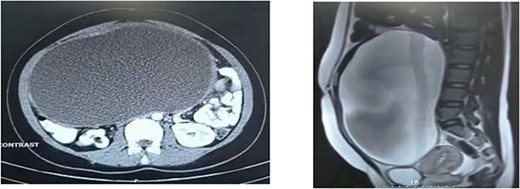

The patient had an ultrasound which demonstrated a cystic lesion with dimensions of 220 × 120 mm. Computed tomography (CT) scan and magnetic resonance imaging of the abdomen and pelvis were requested for further examination, which revealed an adnexal lesion in the form of a giant ovarian cyst (Fig. 1).

CT scan of the abdomen represents an extension of the mass in two specific views. (a) From the front of the lumbar vertebra to the abdominal wall in horizontal view. (b) Below the peritoneal cavity to the above the bladder in sagittal view.